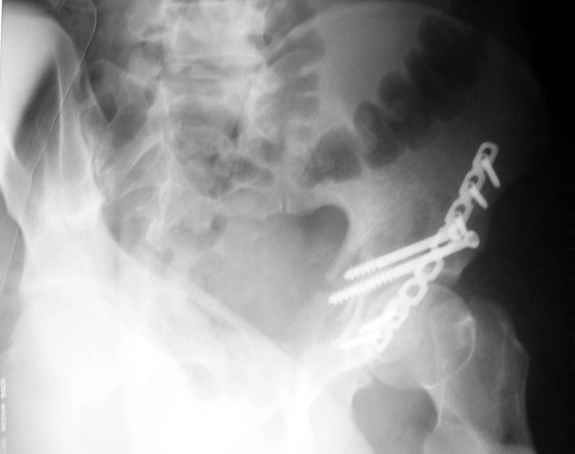

Высылаю пример еще одного случая, остеосинтез пластиной из подвздошного доступа.